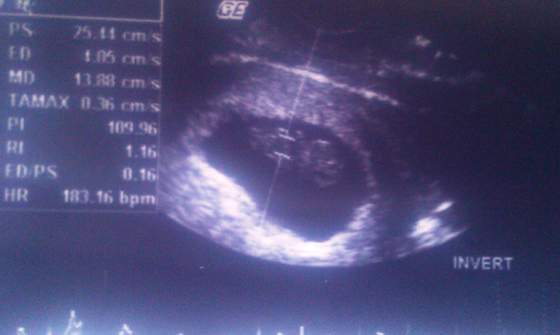

Ból powoli zaczął się zmniejszać, na 15 wczoraj pojechałam do gin, okazało się że z maluchem wszystko w porzadku, ale odetchnęłam, bardzo się bałam!

nawet rączką nam pomachał!

8t4d.jpg8t4d_16102012.jpg8t4d_16102012a.jpg